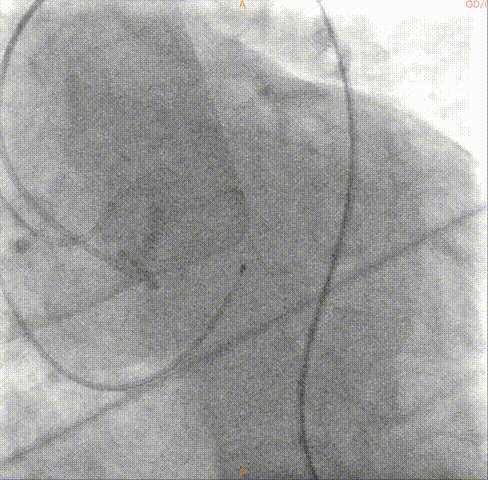

导丝跨瓣

球囊预扩